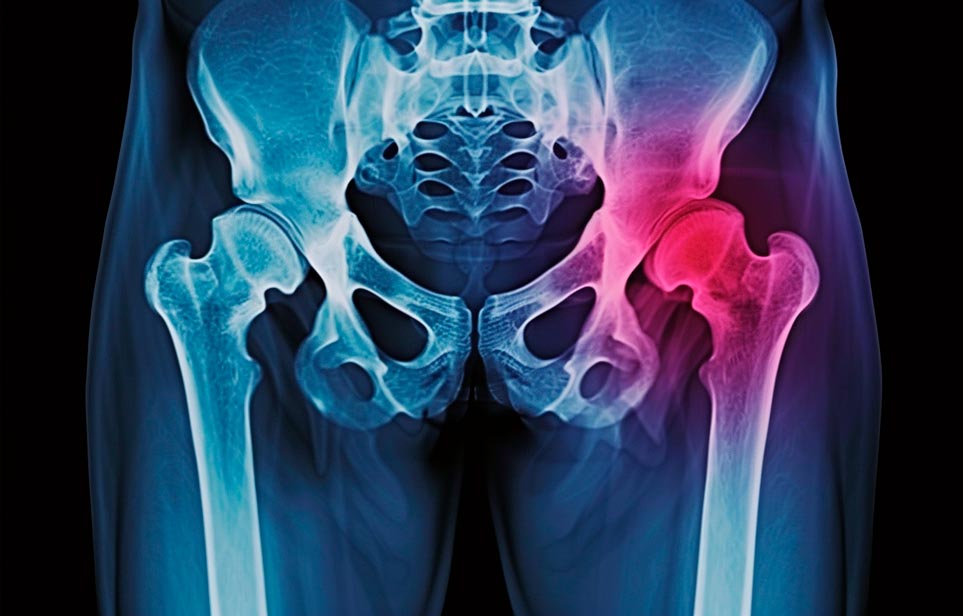

Реабилитация пожилых после перелома шейки бедра в Керчи

Эффективная и профессиональная реабилитация после перелома шейки бедра в Керчи осуществляется по демократичным ценам лучшими специалистами современной медицинской клиники «Заботливые люди» с применением персонального подхода к каждому пожилому человеку с такой тяжёлой травмой бедренной кости ноги. В процессе осуществления такой специализированной услуги все наши пациенты имеют возможность получения качественного и достойного обслуживания, эффективного восстановления. Лучший дом престарелых позаботиться о Вашем близком человеке.

Такая травма в большей части случаев возникает у граждан преклонного возраста. При её появлении на протяжении длительного времени сохраняются болевые и неприятные ощущения в области паха, при которых серьёзно ухудшается качество жизни, возникает множество последствий для его жизни и здоровья.

По какой симптоматике можно определить перелом шейки бедра?

Выявить его можно по возникновению следующей тревожной симптоматики:

- Визуально повреждённая нога сокращается на несколько сантиметром из-за сокращения мышц.

- Стопа выворачивается наружу.

- В лежачем положении человек не может поднять ногу.

При такой симптоматике важно незамедлительно обращаться к специалистам для получения всей необходимой помощи, терапии и восстановления после перелома шейки бедра. Если не оказать помощи старику, то это приведёт к гноению, инвалидности, иным видам осложнений.